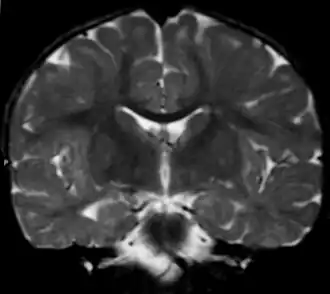

Imagen de una leucodistrofia en una niña de 18 meses. Posible Enfermedad de Alexander | ||

El diagnóstico había sido durante mucho tiempo difícil, debido a que la mayoría de los signos podían darse también en otras leucodistrofias, de modo que la prueba diagnóstica de confirmación consistía en una biopsia cerebral que revelara las fibras de Rosenthal. En ocasiones esto se efectuaba post mórtem en la necropsia. Sin embargo, esta prueba resulta bastante invasiva y se vio la necesidad de buscar otras posibilidades aprovechando las nuevas técnicas de imagen por MRI. En marzo de 2001 la eminente neuróloga Marjo van der Knaap y su equipo pudieron establecer una serie de criterios que probaban en un 90% de los casos la existencia de la enfermedad.[11] Se considera que la presencia de al menos 4 de los siguientes criterios dan un resultado diagnóstico positivo:

- Presencia de anormalidades extensas en la materia blanca con una preponderancia frontal o bien en cuanto a la extensión de estas anormalidades, en el grado de abultamiento, en el grado de cambio de señal o en el de pérdida de tejido (por atrofia o degeneración cística).

- Presencia de un borde periventricular de descenso de intensidad de señal en las imágenes potenciadas en T2 y elevación de la intensidad en imágenes potenciadas en T1.

- Anormalidades en los ganglios basales y tálamos, consistentes en una elevación en la intensidad de la señal y abultamiento o en atrofia y aumento o descenso de la intensidad de la señal en imágenes potenciadas en T2.

- Anormalidades en el tronco encefálico, en particular incluyendo el cerebro medio y la médula.

- Aumento de contraste que implica uno o más de las siguientes estructuras: borde ventricular, cerco de tejido periventricular, sustancia blanca de los lóbulos frontales, quiasma óptico, fórnix, ganglios basales, tálamo, núcleo dentado y estructuras troncoencefálicas.